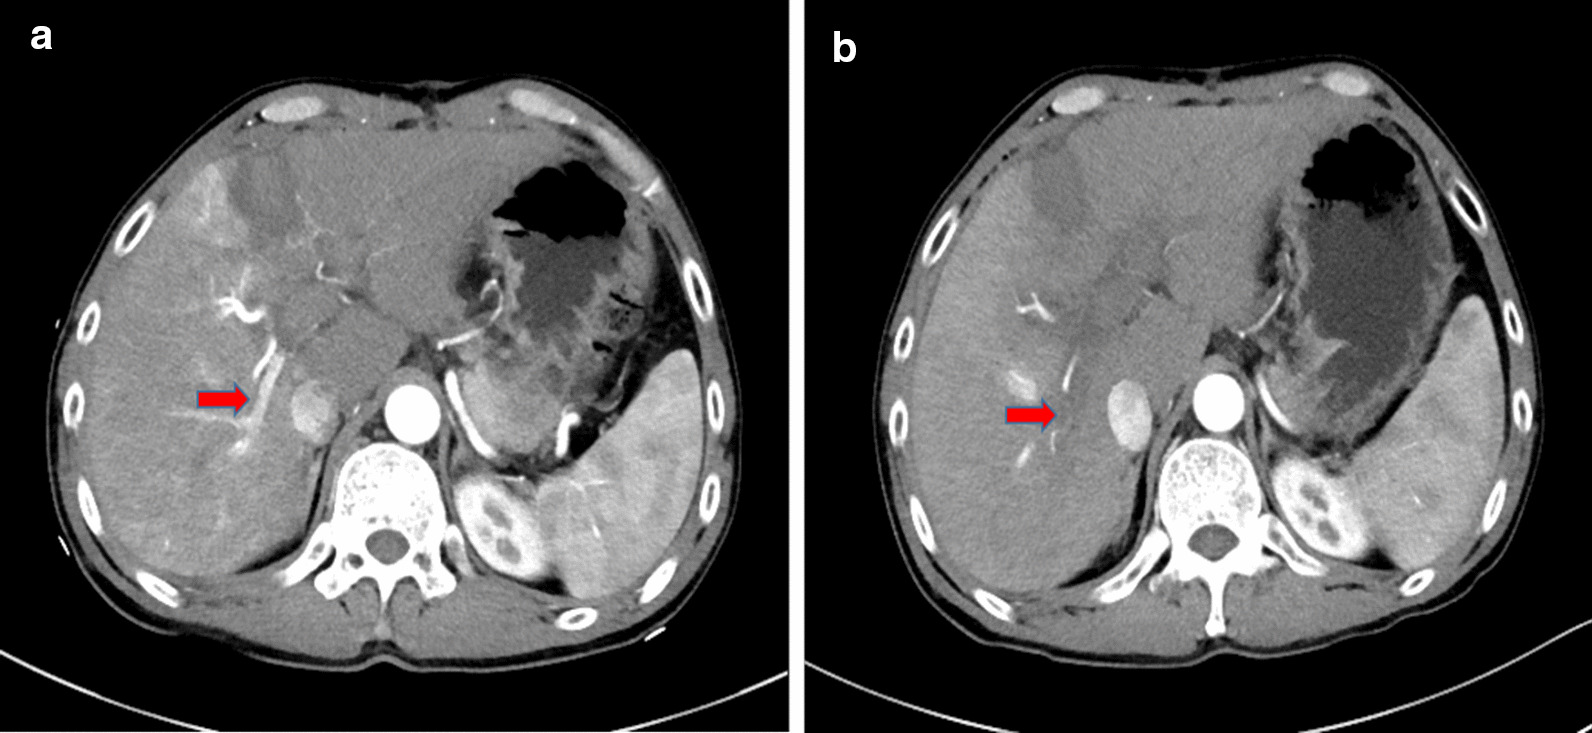

After RALPPS stage-1, the FLR volume was measured by contrast-enhanced CT at roughly 1-week intervals. If the FLR remained < 40% at the second or third evaluation after RALPPS stage-1, rescue RFA/PEI was considered to induce an artificial damage. All rescue procedures were carried out percutaneously under conscious sedation anesthesia with the guidance of ultrasound. Arterioportal shunts (APS) between the ligated right portal vein and the hepatic artery were diagnosed on the contrast-enhanced CT and ultrasound (CE-US) examinations performed after stage 1 (Fig. 1a). When performing rescue PEI, an ultrasound-guided percutaneous PEI with 10 mL of 99% ethanol injected to the reopened portal vein was performed to abolish the APS (Fig. 1b). The ethanol was injected carefully and slowly at a rate of around 2 mL/min through a PTC-B needle (18 G). For patients without APS, RFA was performed for liver tumors located in the deportalized lobes using LDRF-120S (Lead Electron Corp., Mianyang, Sichuan, China) with a RFA duration of 18–20 min (about 6 min per session, 3 sessions). When carrying out the procedure, an RF electrode was inserted into the center of the tumor with an initial power of 50 W, and it was then stepwise withdrawn 1–2 cm for each session. As rescue RFA was not performed for the purpose of the entire tumor ablation, multiple electrodes or multi-site ablations were not required.

Fig. 1.

a First week after the RALPPS stage-1, ultrasound imaging showed an arterioportal shunt (APS) in the right ligated lobes [red arrow]. Note: RALPPS, radiofrequency-assisted ALPPS (associating liver partition and portal vein ligation for staged hepatectomy). b After three sessions of rescue percutaneous ethanol injection (PEI) with 10 mL ethanol each time, the APS disappeared [red arrow]